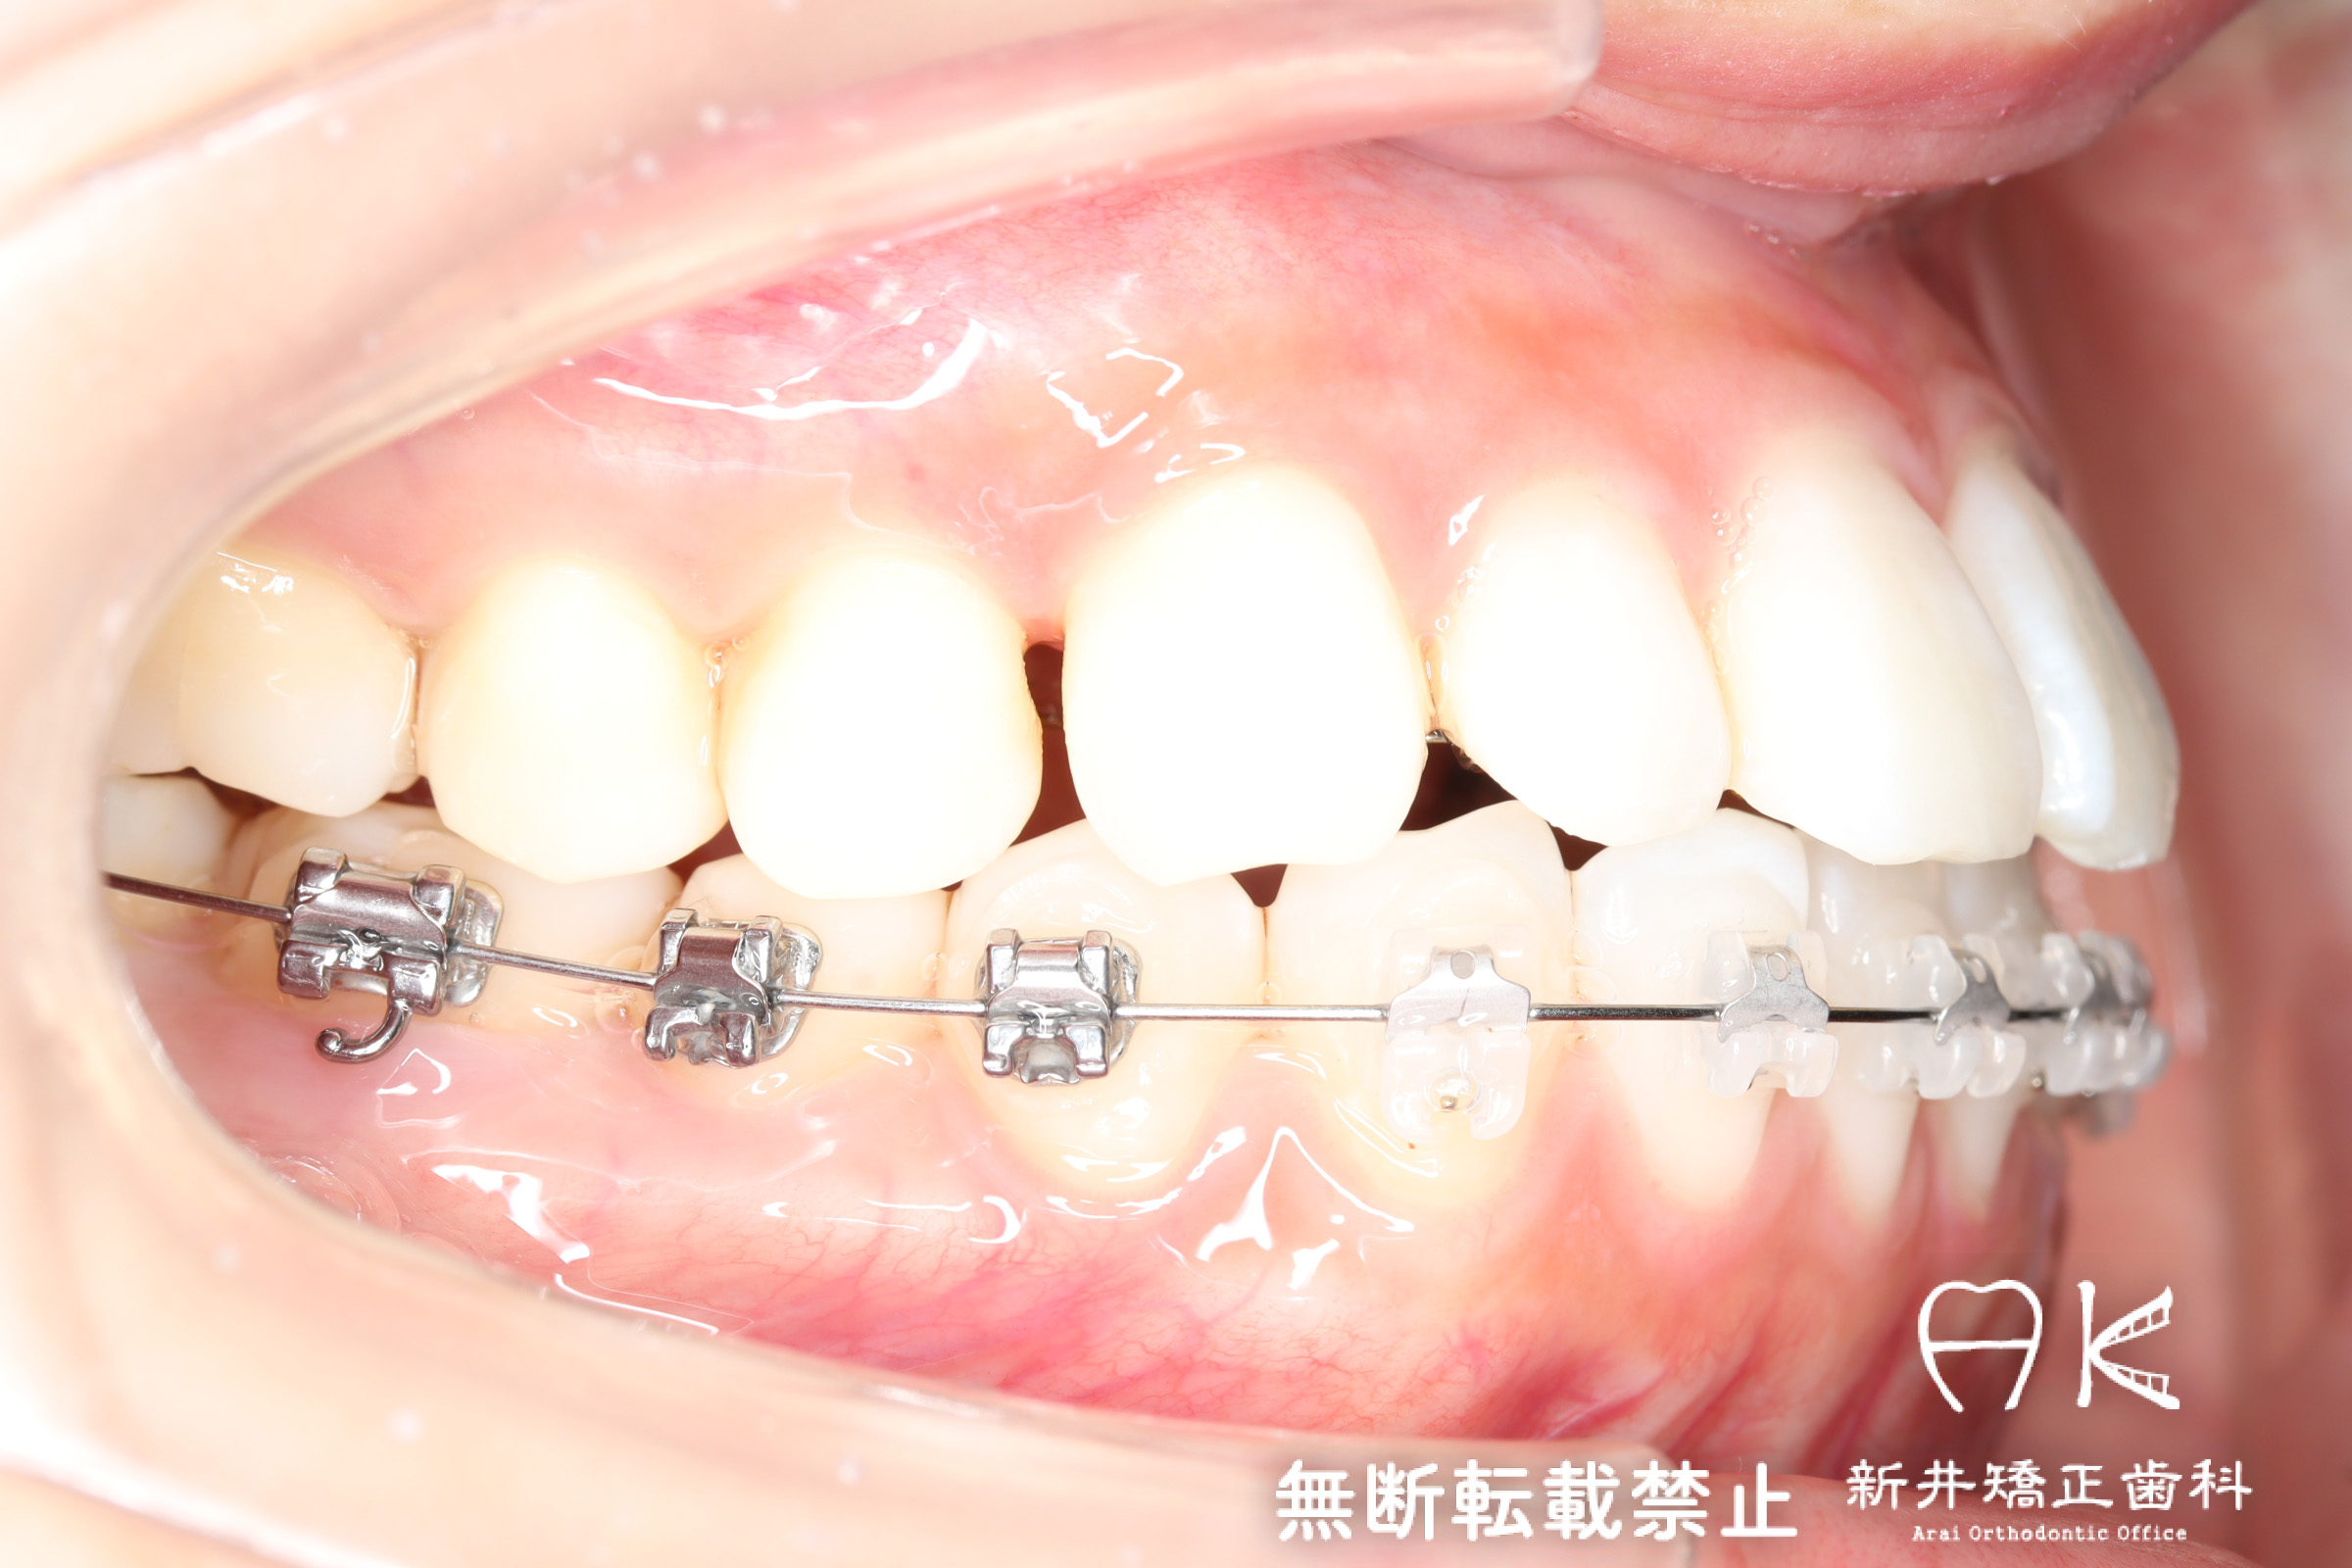

治療中

治療内容

| 使用矯正装置 | セルフライゲーションリンガルブラケット セルフライゲーションブラケット(セラミッククリッピー) 歯科矯正用アンカースクリュー |

| 治療前 | でこぼこしている歯による歯磨きのやりにくさや、奥歯がしっかり咬んでいない鋏状咬合(すれ違い咬合)。 出っ歯による口の閉じにくさ(口唇閉鎖不全)と、正面から見た時のオトガイ部にできる梅干し様のシワやイーラインから飛び出た口元(口ゴボ)。 機能面も審美面も気にしていた患者さんです。 治療中もなるべく装置を目立たせたくないため、ハーフリンガルでの治療となりました。 |